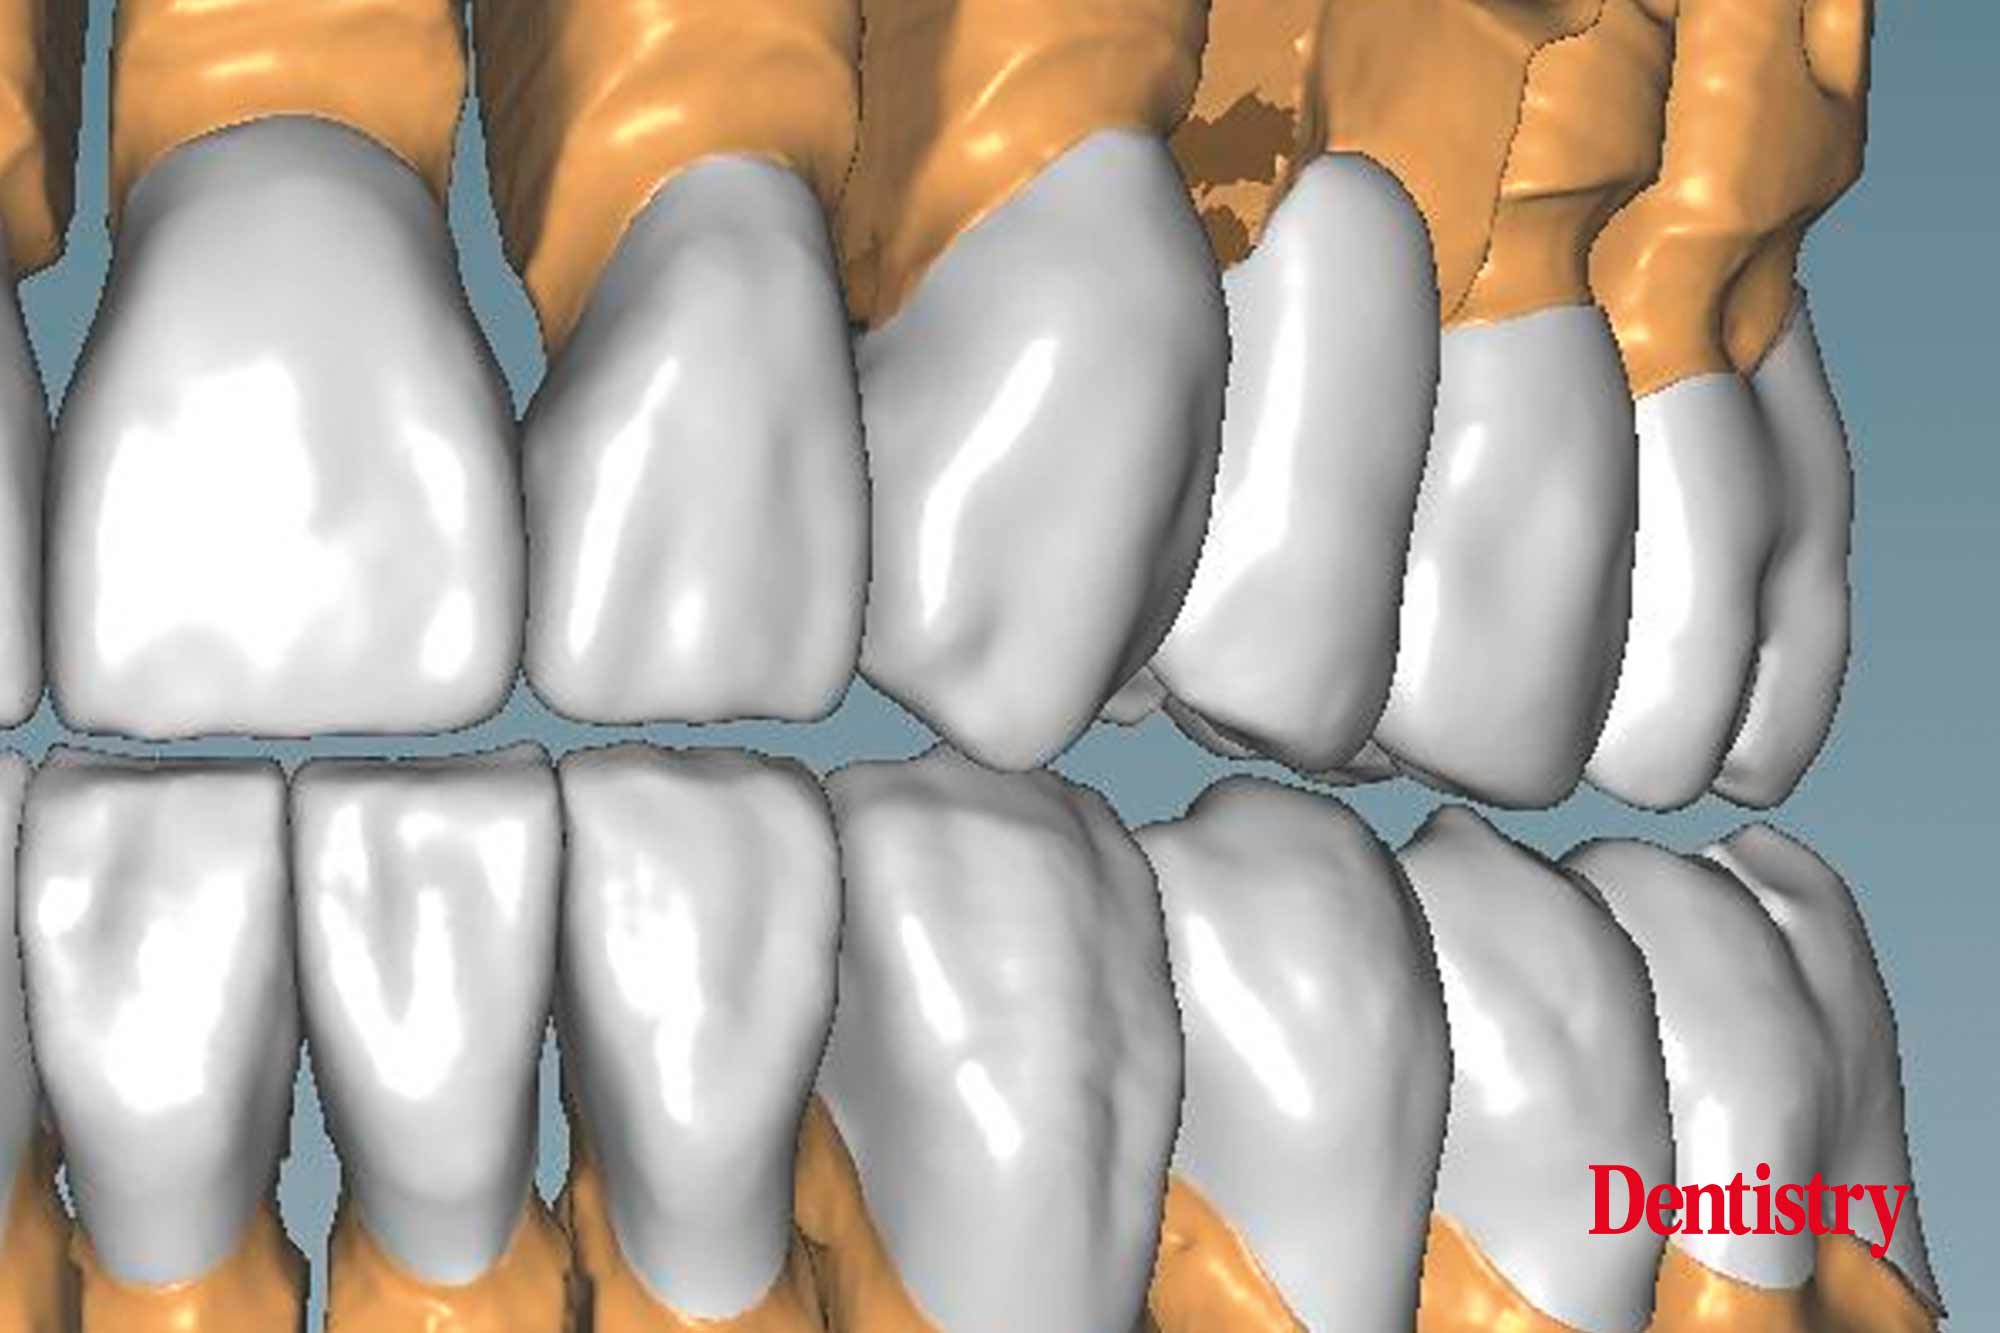

CAD design of the final crowns

Using the CAD software (Figure 12), we were able to round off and refine the areas on the temporary crowns that had been ground and modified intraorally. As a result, this left the remaining areas unchanged.

Figure 13 shows the areas that were adjusted intraorally in green and the remaining unchanged areas in blue. The plan was to fabricate Ceramill Zolid FX crowns on the maxillary teeth first. This is so subsequent corrections on the lower temporary crowns would mean that less corrections would be necessary for the final lower crowns.

Canine guidance with a light group function was created on the Ceramill Mind Wizard.